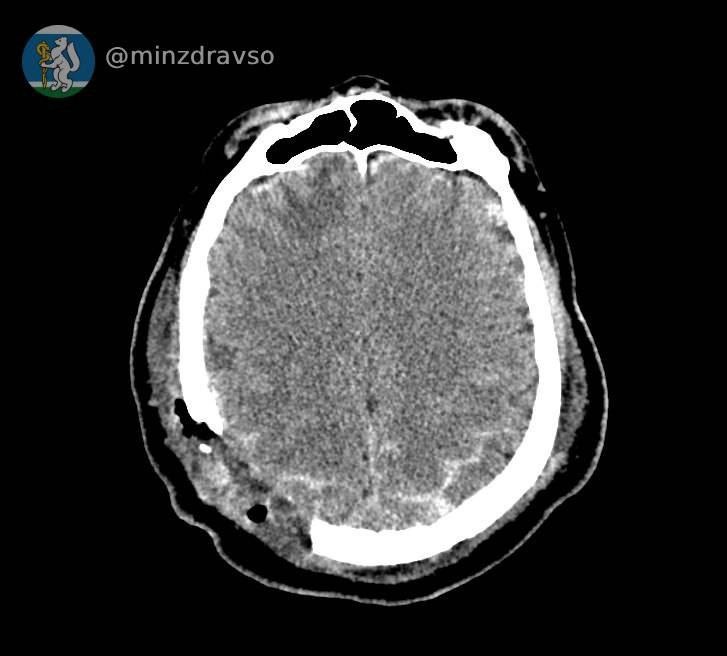

😱Когда стрела строительного крана ударила уральца, его череп буквально раскололся. В критическом состоянии мужчина поступил в единственное на севере нашего региона стационарное отделение скорой медицинской помощи, действующее на базе Серовской городской больницы. Компьютерная томография показала, что мозг повреждён отломками костей, самый острый из которых мог в любую минуту стать причиной гибели пострадавшего...